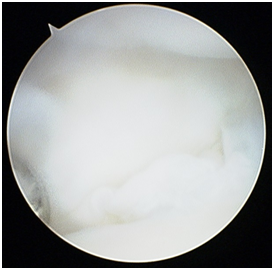

Radio-carpal arthroscopy was done with the 3-4 (between the 3rd and 4th dorsal extensor compartments) portal as the viewing portal and the 4-5 (between the 4th and 5th dorsal extensor compartment) portal as the working portal. The joint was very difficult to scope due to the findings of a “snowstorm” of fibrotic plica bands (Figure 1), thickened synovium covering the TFCC (Figure 2) and further synovitis in the ulno-carpal recess (Figure 3). After debriding all these layers of tissues, the TFCC was found to be intact but stretched over the congenitally deformed ulnar head (Figure 4). There was also early stage chondromalacia of the lunate fossa of the radius.

Figure 4 Radio-carpal arthroscopy left wrist (lunate on top, radius at the bottom) probe on the intact TFCC once the plica bands and thickened synovium have been debrided.